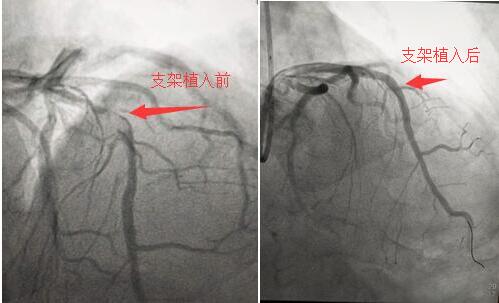

5月10日晚上19時(shí),心內(nèi)科導(dǎo)管室剛剛結(jié)束一例急性下壁心?;颊叩氖中g(shù),宋宜生副主任還沒來得及脫下沉重的鉛衣,“叮鈴——”一陣急促的電話鈴聲響起,“宋主任,急診科送來一例急性心梗的患者!”他立即把白大褂套在已經(jīng)被汗水浸濕的洗手衣上,快步回到病房,與值班的張龍副主任醫(yī)師、路艷主治醫(yī)師床旁查看患者,在確認(rèn)各項(xiàng)檢查結(jié)果后,立即安排手術(shù)人員進(jìn)行急診手術(shù)準(zhǔn)備。術(shù)中,患者生命體征極不穩(wěn)定,心率、血壓不斷下降,陣發(fā)性室性心動(dòng)過速頻繁出現(xiàn)。冠脈CAG顯示:前降支99%狹窄,回旋支95%狹窄,右冠狀動(dòng)脈100%堵塞,為嚴(yán)重的三支病變!“時(shí)間就是心肌,時(shí)間就是生命!宋宜生主任醫(yī)師、張龍副主任醫(yī)師、陳文璐主治醫(yī)師在手術(shù)臺(tái)上嫻熟的操作,郭紀(jì)文主管護(hù)理師快速的傳遞各種器械,并認(rèn)真記錄,王琴麗護(hù)士則守在患者身旁,根據(jù)監(jiān)護(hù)儀上的各項(xiàng)數(shù)據(jù)輪換地調(diào)節(jié)四路液體的速度。手術(shù)室里的氣氛緊張有序,終于,歷經(jīng)四十分鐘同死神的“爭奪戰(zhàn)”,患者的心律轉(zhuǎn)為竇性心律,血壓110/62mmHg,心率76次/分,患者的胸痛、胸悶癥狀逐漸消失。當(dāng)患者安返病房后,又一例診斷為心梗的患者被“120”急救車送入病房,這時(shí)已經(jīng)接近凌晨,但是手術(shù)小組人員仍然在緊張的工作著,顧不上喝一口水,汗水浸透了他們的頭發(fā)和身上的洗手衣……經(jīng)過一個(gè)小時(shí)的手術(shù)后,第三位急性心梗患者的血管被開通,又一條鮮活的生命得以挽救。這時(shí),已是5月11日的凌晨一點(diǎn),新的一天開始了。